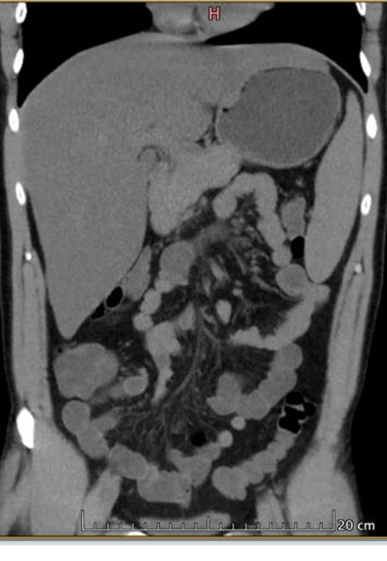

En la tomografía de abdomen se observó hepatomegalia y asas intestinales distendidas (ver figura 2). Estos resultados confirman la coinfección por dengue y malaria. La presencia de anticuerpos IgG e IgM positivos para dengue sugiere una infección reciente o activa, mientras que la prueba rápida de antígenos y la gota gruesa positivas para Plasmodium falciparum confirman la malaria. La trombocitopenia (baja cantidad de plaquetas) es común en ambas infecciones y contribuye a la gravedad del cuadro clínico. La tomografía que muestra hepatomegalia y asas intestinales distendidas indica complicaciones adicionales asociadas a estas infecciones, como el agrandamiento del hígado y la distensión intestinal, lo cual puede estar relacionado con el impacto sistémico de ambas enfermedades.

Figura 2. Tomografía de abdomen

Fuente: Departamento de Imagenología, Hospital de Especialidades Portoviejo.